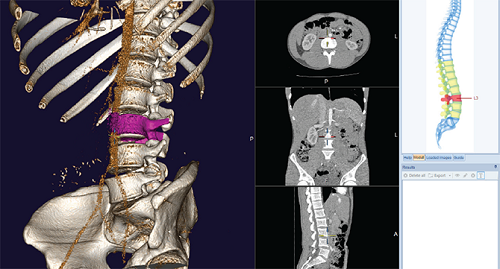

3. Phần mềm 3D Spine cung cấp kế hoạch nắn chỉnh xương trên sơ đồ đốt sống

Để điều chỉnh các kyphose tầm ngắn và dài, cong và vẹo cột sống với mục đích khôi phục cấu trúc cột sống hài hòa, phần mềm chấn thương chỉnh hình 3D Spine cung cấp kế hoạch nắn xương trên đốt sống.

Bác sĩ có thể thực hiện một hoặc nhiều ca nắn xương bằng cách chỉ định các vết cắt hoặc vùng cắt riêng lẻ. Các khu vực được cắt bỏ có thể được xoay vòng hoặc di chuyển theo yêu cầu. Tất cả các phép đo được tự động điều chỉnh và phản ánh tình trạng mới sau khi thực hiện hiệu chỉnh.

Mô phỏng tùy biến các đường cắt xương với điều chỉnh linh động với tất cả các góc tương ứng

Các phương án phẫu thuật khác nhau có thể được mô phỏng và thử nghiệm, tìm ra phương án lý tưởng cho bệnh nhân. Nhờ lập kế hoạch kết hợp, tất cả các ca chỉnh xương được thực hiện trên hình ảnh 3D sẽ được tự động chuyển sang hình ảnh 2D và ngược lại.

Lịch sử công việc được thực hiện trên hồ sơ Cagittal của bệnh nhân được theo dõi và minh họa theo thời gian thực. Bác sĩcó thể thực hiện căn chỉnh tự động dựa trên các thông số đã đo trước đó sau khi thực hiện phẫu thuật nắn xương.

Cấu hình cột sống hài hòa có thể được tự động khôi phục do phần mềm chỉnh hình 3D Spine có thể đề xuất góc cắt tối ưu.